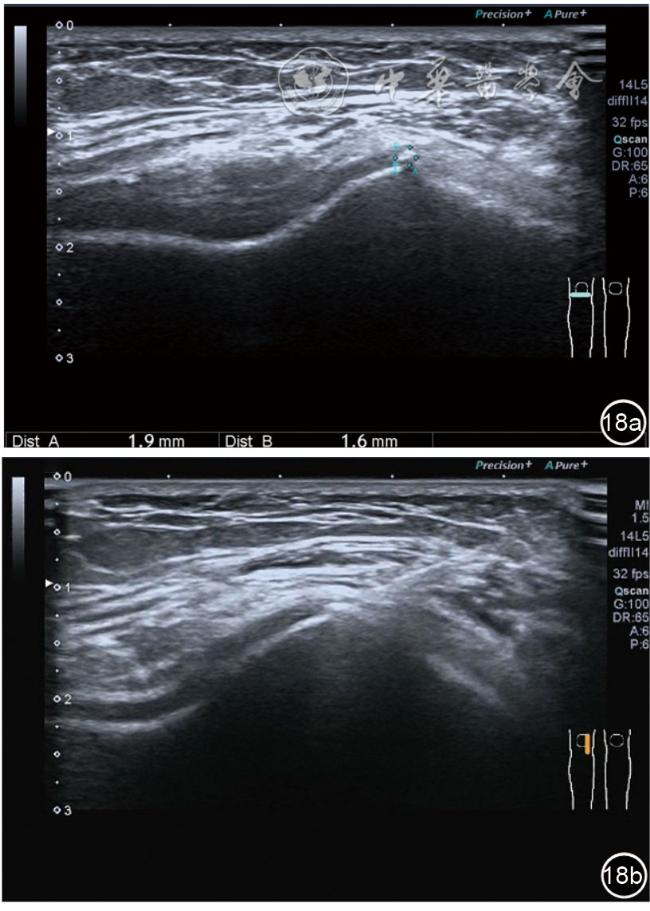

3.膝关节内局部治疗。随着病情发展,静态结构失衡,膝关节内部结构发生变化,会出现软骨损伤、脱落,关节间隙变窄,内外间隙不等,骨赘形成等。膝关节内局部治疗包括关节内症状性骨赘剥离、玻璃酸钠及PRP注射等。(1)膝关节内症状性骨赘针刀剥离松解治疗。由于软骨缺损或者力平衡失调,在关节内脱落软骨区会出现骨赘。部分骨赘引起疼痛,或者与髌骨撞击出现临床症状需要治疗。针刀剥离目的不是去除骨赘,而是剥离松解,缓解或者消除疼痛。以股骨外髁骨赘为例。患者平卧位,膝关节屈曲100°~120°。一般选用10 MHz超声探头,穿刺区域常规消毒,探头涂抹耦合剂后套入无菌手套碘伏消毒或使用无菌耦合剂。将探头置于患者皮肤表面,短轴扫查,显示关节面与骨赘,选用25G注射针,抽吸1%利多卡因3 ml于骨赘周围进行分层麻醉。选用直径1 mm的Ⅰ型2号针刀,在超声引导下从外侧向内侧到达骨赘,反复剥离,一般5~8刀后拔出针刀结束治疗(图18),局部压迫5分钟,无菌敷料覆盖。(2)膝关节髌上囊积液治疗。髌上囊积液在膝关节骨关节炎比较常见,尽管积液量可能很大,但通过软组织松解治疗后,大部分患者积液会减少或者消失。所以积液的治疗可以放在后面处理。超声引导下抽出积液,药物注射是常用的治疗方法。膝关节炎积液的治疗通常包括关节内皮质类固醇激素或者臭氧注射。如果慢性以滑膜丛型增生为主,针刀有限切割增生滑膜加药物注射可提高疗效。①髌上囊积液抽吸加臭氧注射治疗。患者平卧位,膝关节屈曲30°~60°,膝下垫一软枕。选用10 MHz超声探头,治疗前消毒准备同骨赘针刀剥离松解治疗。将探头置于患者皮肤表面,短轴扫查,找到积液最多处,应用22G针头,直接穿刺进入髌上囊抽出液体,然后根据髌上囊大小制备35 μg/L的15~20 ml臭氧注入髌上囊内拔出针头(图19),局部压迫2分钟,无菌敷料覆盖。②髌上囊慢性滑膜炎针刀切割松解治疗。患者平卧位,膝关节屈曲30°~60°,膝下垫一软枕。选用10 MHz超声探头,治疗前消毒准备同骨赘针刀剥离松解治疗。将探头置于患者皮肤表面,长轴或短轴扫查,找到积液最多处,用一次性5 ml注射器抽吸1%利多卡因3 ml于髌上囊进行分层注射麻醉,囊内也要注射适量麻药,尽量抽出积液。选用直径1 mm的Ⅰ型2号针刀,长轴扫查从近端向远端,短轴扫查从外侧向内侧,在超声引导下进入囊肿内对内壁及增生滑膜的不同方向、角度进行反复切割(图20),一般2~3分钟拔出针刀,然后囊内注射1%利多卡因3 ml+曲安奈德15 mg,结束治疗,局部压迫5分钟,无菌敷料覆盖。(3)膝关节腔PRP注射治疗。关节腔注射主要是为了修复软骨,如果不是为了治疗积液,不主张应用激素类药物。目前主要的注射药物为玻璃酸钠、PRP。按照传统的注射部位,多为髌上内、外或者髌下内、外注射点,但是超声不能观察到注射针的位置,药物也不能很好到达软骨损伤的部位,效果受到影响(图21)。膝关节软骨损伤的主要部位在髌股关节的股骨髁,超声可以很好地显示这一部位,并能显示软骨变薄。因此,由这个路径平面内进针注射,可以很好显示穿刺针的路径与位置。以注射PRP为例。患者平卧位,膝关节屈曲100°~120°,选用10 MHz超声探头,治疗前消毒准备同骨赘针刀剥离松解治疗。将探头置于患者皮肤表面,短轴扫查显示关节面,应用25G注射针头,抽吸1%利多卡因2 ml由内侧进针进行分层麻醉直达关节软骨面。制备4.5 ml PRP,直接注射到关节面,液体顺关节面分布,注射完毕拔出针头(图22)。局部压迫2分钟,无菌敷料覆盖。(4)髌骨软化超声影像融合技术下PRP注射治疗。髌骨软化是指髌骨关节面的软骨损伤,软骨下骨囊变,MRI能够明确诊断,但是超声不能显示。应用超声与MRI的影像融合技术,依据MRI明确注射部位,在超声引导下可将药物精准注射到软骨损伤的部位。患者平卧位,膝关节屈曲30°,下面垫一软枕。一般选用10 MHz超声探头,治疗前消毒准备同骨赘针刀剥离松解治疗。将MRI的原始图像数据导入超声设备中,进行手动影像融合,完全融合后,确定穿刺靶点,以MRI图像为目标,以超声图像为实时引导进行穿刺,到达目标后,注射提前制取的PRP 3 ml(图23),注射完毕拔出针头,局部压迫3分钟,创可贴覆盖。

图18 超声引导下膝关节内症状性骨赘针刀剥离松解治疗